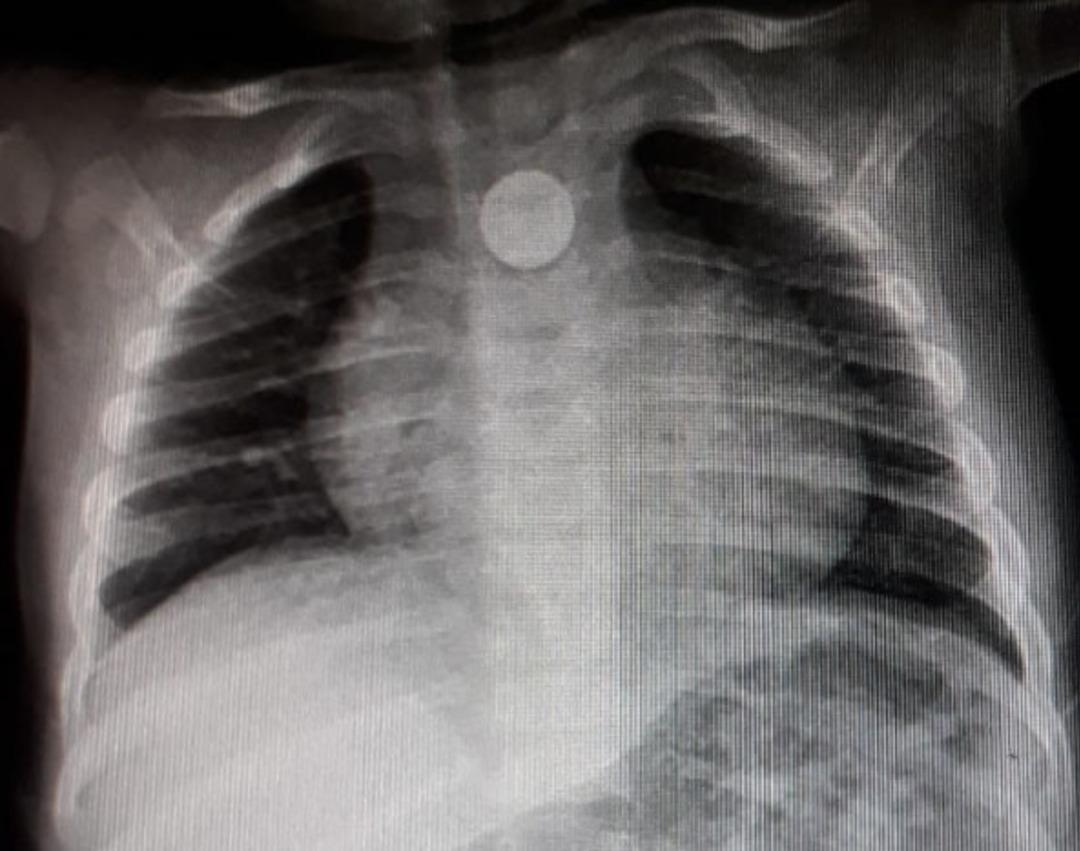

Oyun oynarken yuttuğu para yüzünden ölümle burun buruna gelen 9 aylık bebeğin röntgen filmi çekilince yaşananların nedeni ortaya çıktı. İnegöl Devlet Hastanesi'ne ardından da Bursa Şevket Yılmaz Eğitim Araştırma Hastanesi'ne giden aile, bebeklerinin boğazına takılan para çıkarılınca rahat bir nefes alabildi.